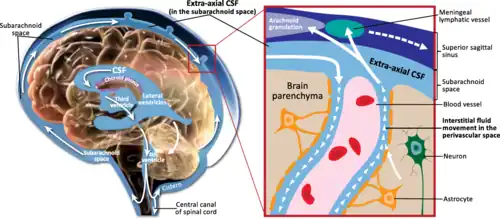

Mechanism

Hydrocephalus is due to an imbalance between the amount of cerebrospinal fluid (CSF) produced and the amount reabsorbed (or removed from the ventricular system).[36] The purpose of cerebrospinal fluid is to provide mechanical support, nutrients, and remove waste from the central nervous system.[23] In a person without hydrocephalus, CSF continuously circulates through the brain, its ventricles and the spinal cord and is continuously drained away into the circulatory system. Alternatively, the condition may result from an overproduction of the CSF, from a congenital malformation blocking normal drainage of the fluid, or from complications of head injuries or infections.[1]

The choroid plexus, located in the lateral ventricles, forms the majority of CSF (believed to be around 70–80%). The ependymal lining of the ventricular system, the subarachnoid space, and the blood-brain-barrier forms the rest.[36]

CSF flows through the ventricular system through the following pathway:[37]

Lateral Ventricles → Interventricular Foramen of Monro → Third Ventricle → Cerebral Aqueduct → Fourth Ventricle

The CSF then exits the fourth ventricle through the median aperture and lateral aperture. It goes into the subarachnoid space or central canal of the spinal cord. Then, it is absorbed by the vili of arachnoid granulations into the blood circulation.[37]

There have also been recent theories and studies exploring the drainage of CSF.[37][38] One theory involves the drainage of CSF into the lymphatic vessel system. The lymphatic vessel system clears proteins and fluid throughout the body, but whether they are involved in CSF drainage within the brain is controversial and not yet clear. Lymphatic vessels in the dura mater is a possible site of CSF drainage.[38]

Cilia plays a role in the flow of CSF. Cilia are long microtubules on the cell membranes of many cells, including ependymal cells (which line the ventricular system). Some genetic causes of congenital hydrocephalus have been linked to issues with cilia.[23]